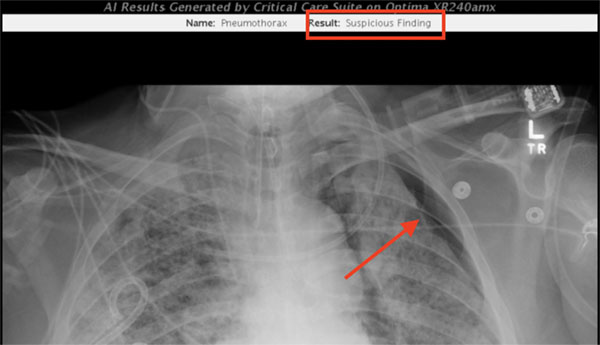

Dr. Mongan shared images (shown below) demonstrating the algorithm identifying a pneumothorax in a recent ICU patient (red annotations were added manually to highlight the findings). Also shown are the results of a separate algorithm measuring the position of the endotracheal tube on the same patient, developed by Valentina Pedoia, PhD, assistant professor and data scientist, Dr. Rachael Callcut, MD associate professor of surgery now at the University of California, Davis, and Sharmila Majumdar, PhD, vice chair of research and executive and scientific director of the ci2, measuring the position of the endotracheal tube on the same patient. Other key participants were radiologist Thienkhai Vu, MD and fellow Rutwik Shah, MD and other investigators from the CDHI. Note, all patient data has been removed.